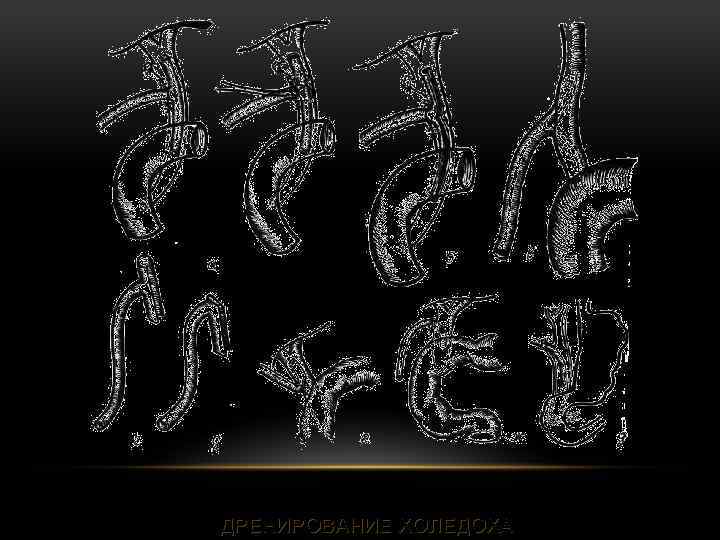

ДРЕНИРОВАНИЕ ХОЛЕДОХА

ДРЕНИРОВАНИЕ ХОЛЕДОХА